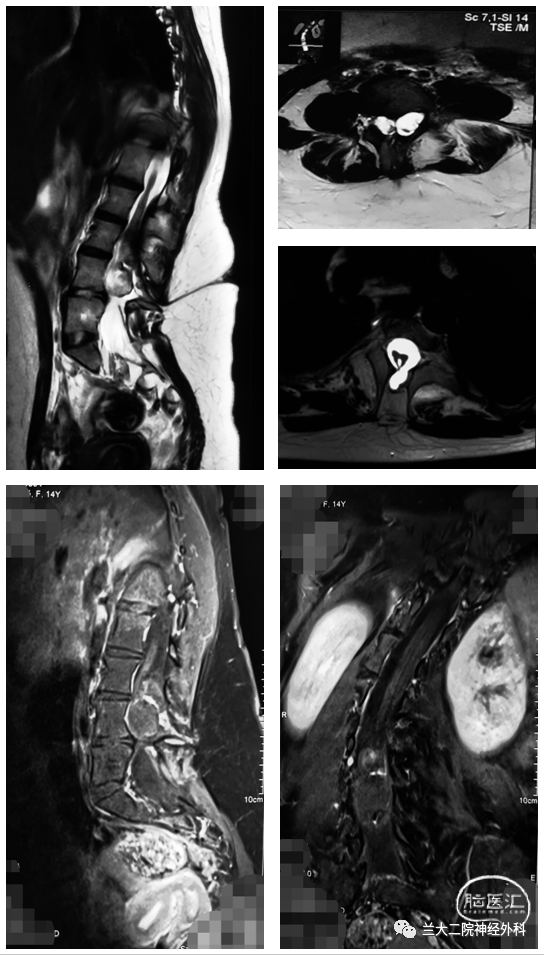

7. 腰骶段皮肤藏毛窦.6. 多节段先天性脊柱裂并蝴蝶椎;5.

图片尺寸544x955